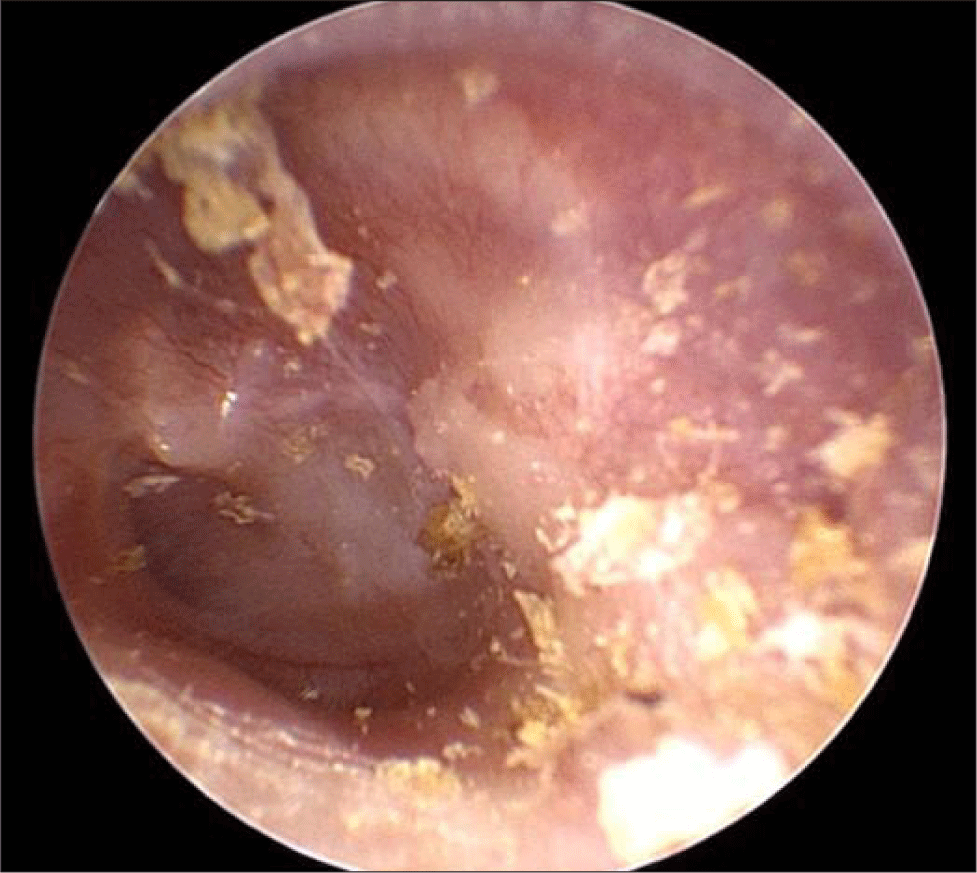

2세 5개월 된 남아가 내원 2개월 전부터 시작된 이루를 주소로 본원 이비인후과 외래에 내원하였다. 진찰 당시 좌측 외이도 내에 육아조직(granulation tissue)이 관찰되었으며(Fig. 1A), 이루에 대한 배양 검사에서 MSSA(Methicillin-sensitive Staphylococcus aureus)가 분리되었다. 이에 항생제 점이약으로 Cetraxal Plus® ear drops(ciprofloxacin 3 mg, fluocinolone acetonide 0.25 mg; Laboratorios Salvat, Barcelona, Spain)을 사용하고, 경구 항생제를 병용하여 치료하였고, 경과 관찰 중 이루는 호전되었으며 육아조직 또한 점차 소실되었다.

그러나 2개월 후 외이도 후방에서 종물이 돌출되는 양상으로 외이도 협착이 관찰되었고(Fig. 1B), 청성뇌간유발반응검사상 우측 30 dBnHL, 좌측 70 dBnHL로 좌측 난청 소견을 보였다. 정밀한 검사를 위해 측두골 전산화단층촬영(computed tomography, CT)을 시행하였다. CT에서는 좌측 유양돌기(mastoid), 측두골 인부(squamous part), 측두하악관절(temporomandibular Joint, TMJ)의 전방 및 상부, 외측 반고리관(lateral semicircular canal) 누공을 포함하는 광범위한 골 파괴성 병변이 확인되었으며, 중이강(middle ear cavity)에도 병변 침범이 확인되었으나 이소골의 파괴 소견은 명확하지 않았다(Fig. 2). 이후 확산 강조 자기공명영상(diffusion-weighted MRI[magnetic resonance imaging])에서는 동일 부위에 확산 제한 소견(diffusion restriction)을 동반한 병변이 관찰되어 진주종을 의심하였다(Fig. 3).